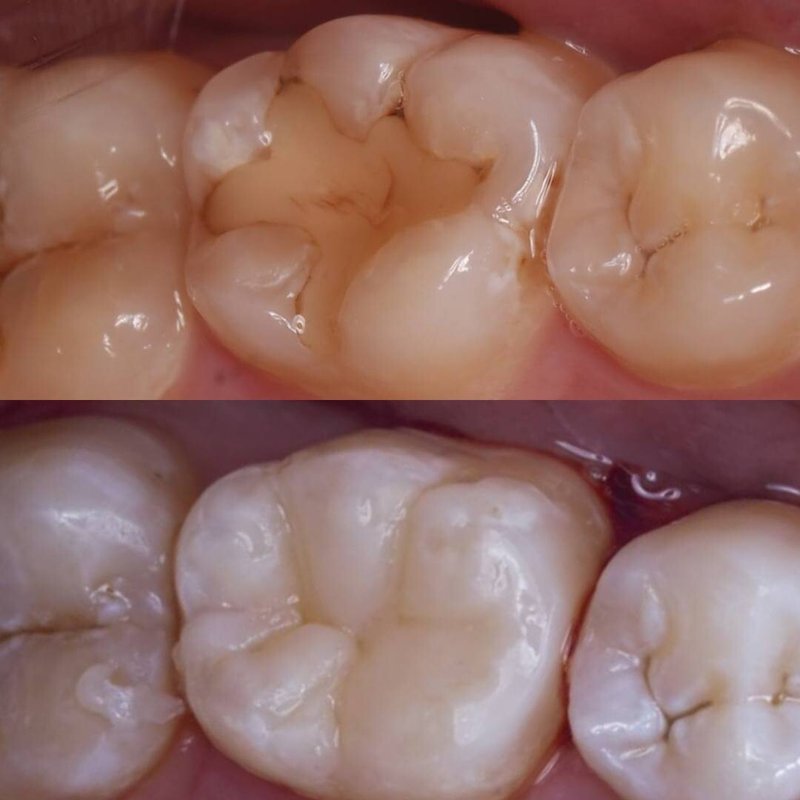

Фотогалерея

Занимается эстетической реабилитацией улыбки путем отбеливания, художественной реставрацией и виниров, а также лечением таких заболеваний, как кариес, пульпит, периодонтит, гингивит, гиперестезия, флюороз и др.

Хочу поблагодарить за прекрасное обслуживание и внимательный подход персонала. Мне делали реставрацию жевательных зубов и пролечили два канала, доктор был очень вежлив и тактичен во время процедур. Все прошло замечательно и никаких болевых ощущений не осталось. После приема мне дали полезные советы по уходу за зубами.